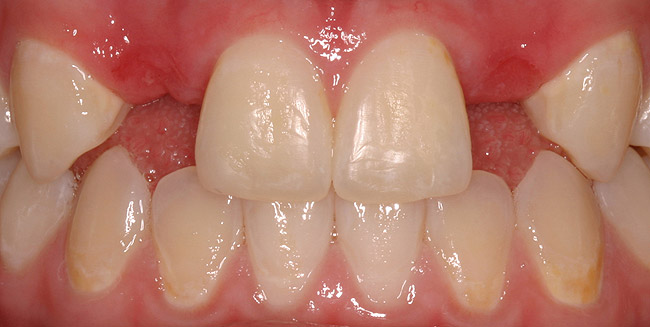

Figure 5d  Completed, porcelain-fused-to-gold implant restorations, custom gold abutments, lingual-set screw-retention, Kerr Extrude¬Æ light-body crown-abutment seal.

Figure 5d

Figure 5e  Completed, porcelain-fused-to-gold implant restorations, custom gold abutments, lingual-set screw-retention, Kerr Extrude¬Æ light-body crown-abutment seal.

Figure 5e

Figure 5f  Completed, porcelain-fused-to-gold implant restorations, custom gold abutments, lingual-set screw-retention, Kerr Extrude¬Æ light-body crown-abutment seal.

Figure 5f

Figure 5g  Completed, porcelain-fused-to-gold implant restorations, custom gold abutments, lingual-set screw-retention, Kerr Extrude¬Æ light-body crown-abutment seal.

Figure 5g